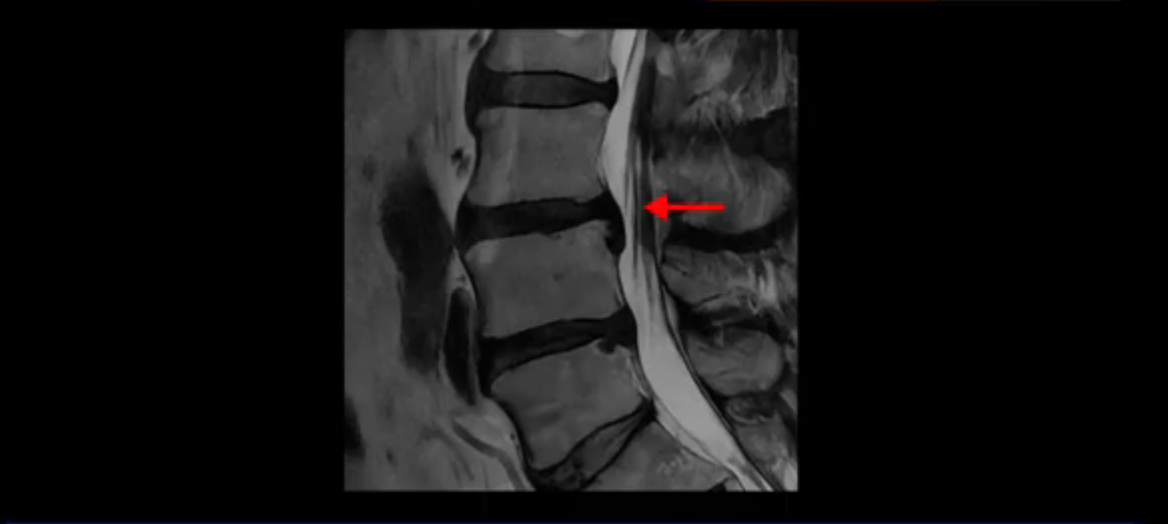

이분 MRI를 잠깐 보실까요? 보시면 두 마디가 특히 안 좋은데 3번 4번 디스크가 터져서 흘러 내려 있습니다.

보시다시피 흘러 내려온 디스크 수핵이 신경 공간의 왼쪽으로 보입니다.